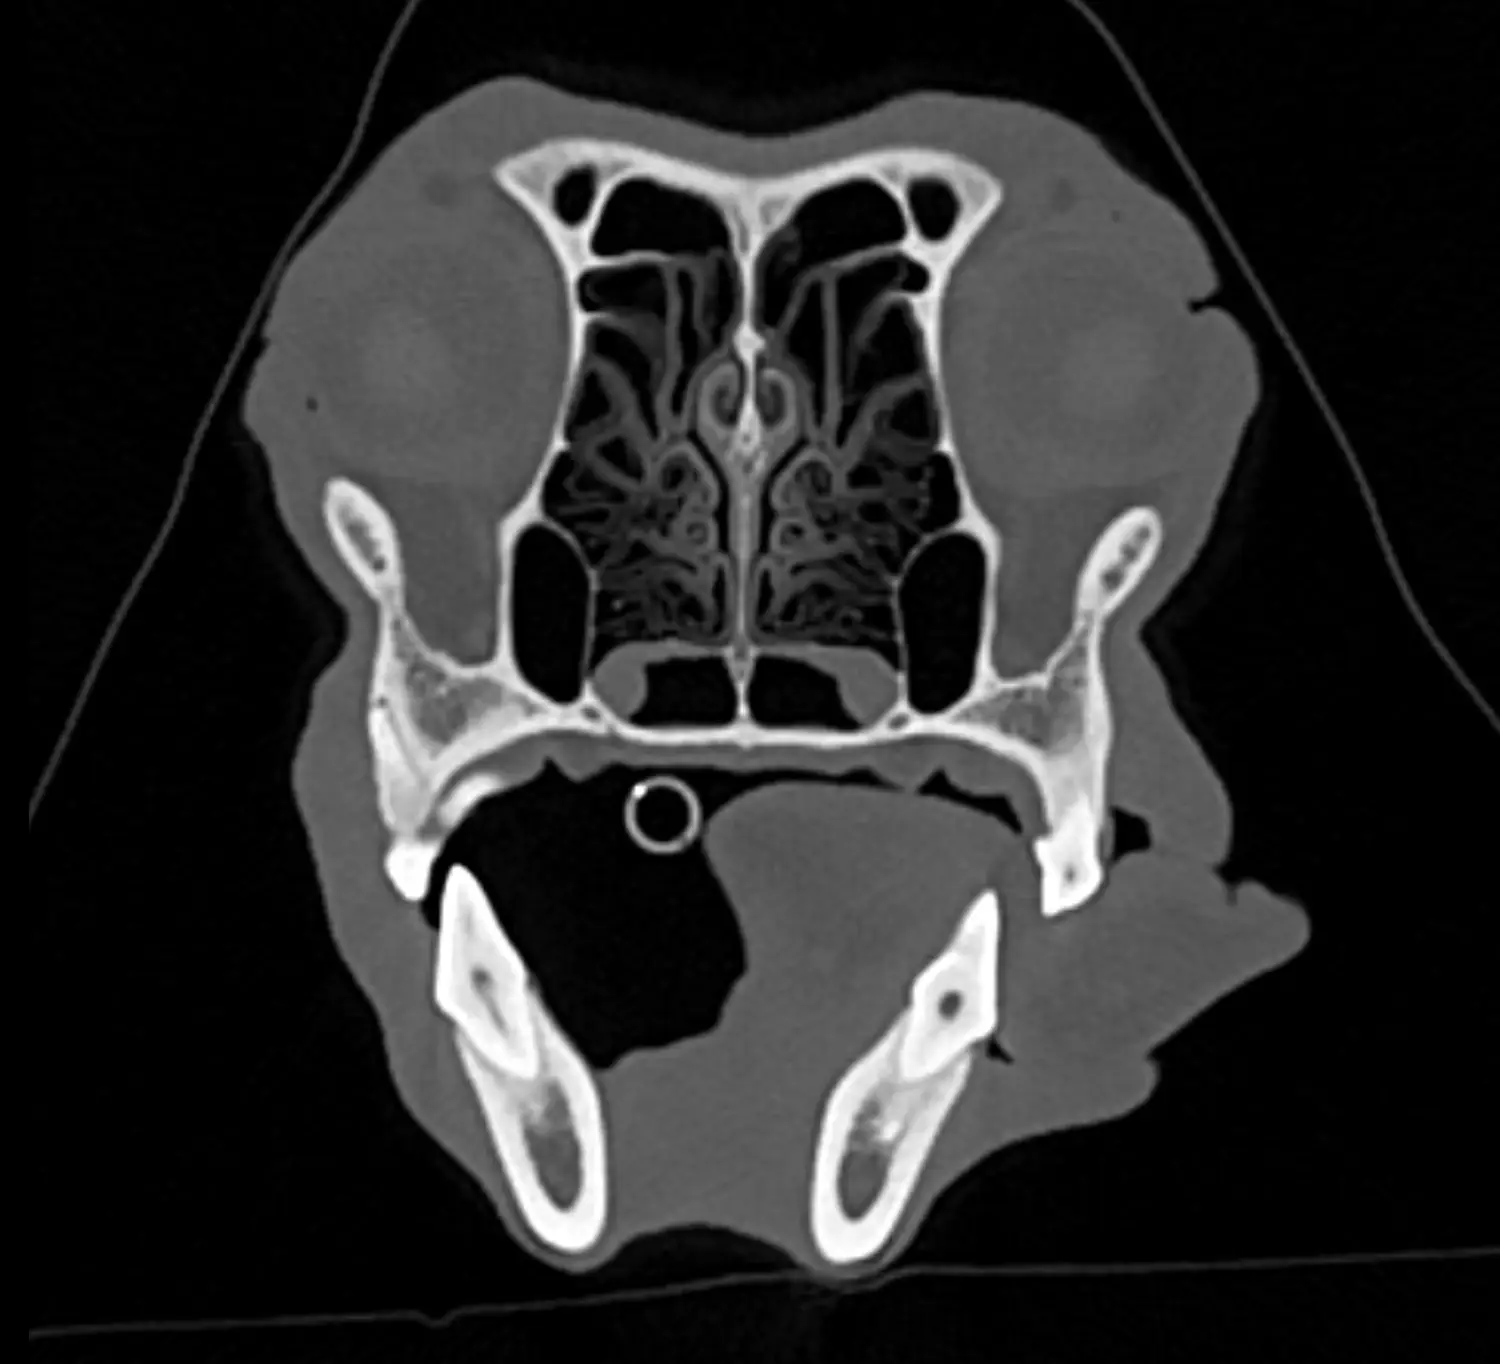

Hlava a krk:

Zobrazení a diagnostika patologií v dutině nosní (nádory, chronické záněty, cizí tělesa). Zlomeniny čelistí. Hluboké procesy v nosohltanu a krku (nasopharyngeální abscesy). Patologie v oblasti oka. Některé nádorové procesy mozku a lebky. Fraktury lebky, krvácení do mozku. Poranění krční páteře. Poranění dýchací trubice či hrtanu.